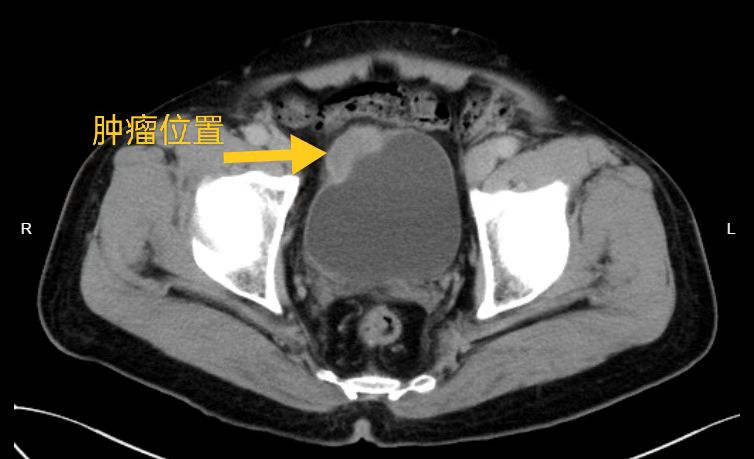

日前,佛冈县石角镇的郭大叔因反复血尿余来我院就诊,泌尿科住院后完善腹部CT增强扫描检查,泌尿外科医生高度怀疑膀胱癌,我院泌尿外科主任、副主任医师刘伟光详细审查郭大叔病史及相关检查资料,决定予静脉全麻下行经尿道膀胱镜检查+膀胱肿物活检术,活检术后证实为浸润性尿路上皮癌。予请省人医泌尿外科主任刘久敏会诊。

右肾肿瘤位置,大小约58mm×59mm×53mm

刘久敏主任会诊后指出,患者完善膀胱肿物病理活检证实为浸润性尿路上皮癌,结合患者盆腔增强CT检查,肿瘤较大,侵犯膀胱壁,须根治性膀胱切除才能治愈病情,避免肿瘤扩散与转移。刘久敏主任与我院泌尿外科团队为郭大叔制定治疗方案:尽早行微创腹腔镜下根治性膀胱切除术+双侧输尿管腹壁造口术。